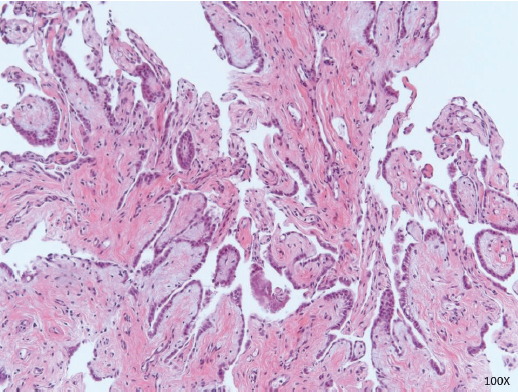

Stains were negative for CK20 and TTF1, consistent with a diagnosis of endometrioid carcinoma. Endometriosis was focally seen embedded within the wall of the ileum and colon, suggesting that the tumor arose in a background of endometriosis (Figure 3). The mesenteric implant demonstrated papillary mesothelial proliferation compatible with WDPM (Figure 4).

FIGURE 4: Papillary mesothelial proliferation. Papillary fronds lined by bland cuboidal mesothelial cells consistent with well-differentiated papillary mesothelioma. This is considered a tumor of uncertain malignant potential (×100 magnification)